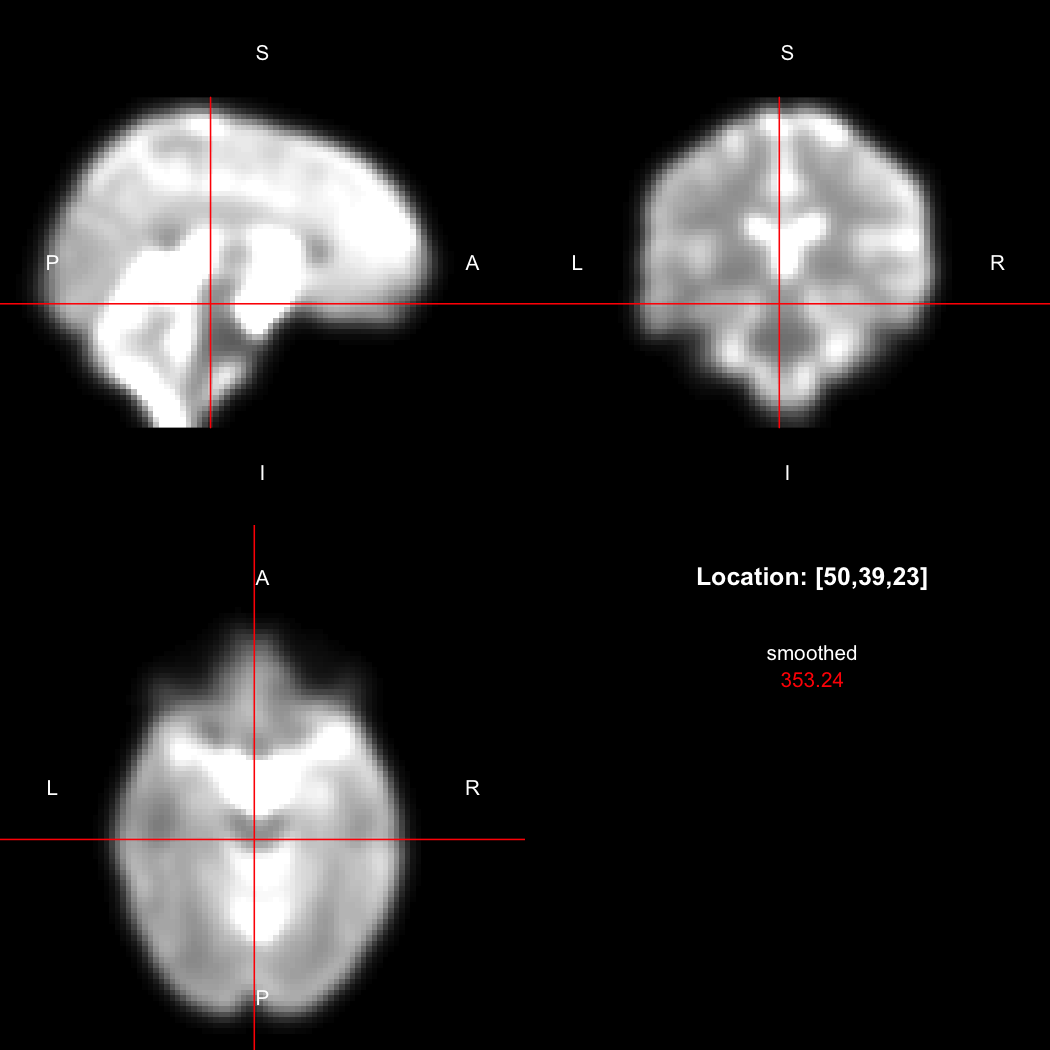

A simple example operation would be to smooth the image with a Gaussian smoothing kernel of standard deviation 4 mm. We can use standard R syntax to perform this operation, return a result, and then show it:

smoothed <- run(smooth_gauss(image, 4))

view(smoothed)

## Setting window to (0, 549.9)

Here, smooth_gauss() requests the smoothing operation,

and run() actually runs the pipeline and returns the

processed image.

However, the pipe syntax provides an alternative, which can be

further simplified because calling view() on a pipeline

will implicitly run it.

image %>% smooth_gauss(4) %>% view()

## Setting window to (0, 549.9)

Notice now smooth_gauss() is now called with only one

argument, and view() with none, because the input to the

pipe (%>%) is implicitly added first. The benefits to